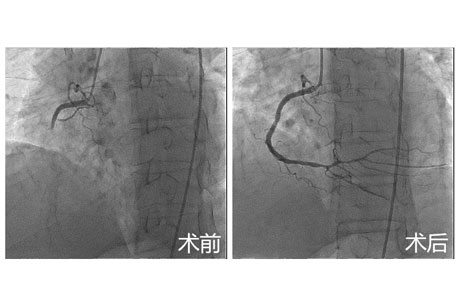

上午9:27,门诊打来电话,要收治一名急性心梗的患者。在CCU,这属于再寻常不过的病种了,却不曾想,这名患者同时患有尿毒症、一侧肾切除,目前每周两次透析…,单纯的急性心肌梗死就是能要人命的,而合并尿毒症,患者死亡风险会多倍的增加,此时最佳的治疗是急诊介入治疗,但合并尿毒症的急性心肌梗死会使介入手术的风险成倍增加,并且我们临床工作中遇到此种情况并不多。怎么办?医生们进退两难,而此时患者胸痛的症状持续加重,所有人都清楚他随时面临着梗死面积扩大导致猝死的风险,情况迫在眉睫……

由北京友谊医院心内专家赵慧强和我院高筱红主任带领的介入团队考虑到此时患者如果不进行再灌注治疗,患者的预后将会非常差,而介入术后会对患者肾功能产生很大不良影响。介入团队商议后认为,术后需要尽快透析,于是立即联系肾内科,第一时间安排好了术后透析事宜,而肾内科同仁的勇于担当和配合也让我们对于打好这场硬仗充满信心。

于是,行术前准备、开通血管…,经历了50分钟,我们整个团队终于松了一口气,手术很成功!